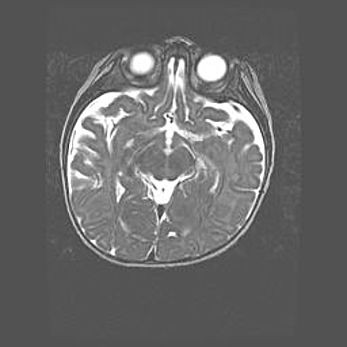

Сообщающаяся гидроцефалия. Кистозная энцефаломаляция головного мозга.

Возраст: 3 месяца 4 дня

Вес: 3100 г

Пол: женский

Окружность головы: 34 см

Срок гестации: 31 неделя

Кистозная энцефаломаляция головного мозга - одна из форм поражения головного мозга в детском возрасте. Характеризуется возникновением множественных и распространённых кист в коре, белом веществе и подкорковых образованиях головного мозга у плодов, новорождённых и детей раннего возраста. Развитие кистозной энцефаломаляции связано с внутриутробной асфиксией и гипотонией, родовой травмой, тромбозом синусов, пороками развития сосудов, инфекциями, сепсисом и другими причинами. Наиболее значимые инфекционные агенты: вирусы простого герпеса, цитомегалии, краснухи, токсоплазмы, энтеробактерии, золотистый стафилококк и другие.